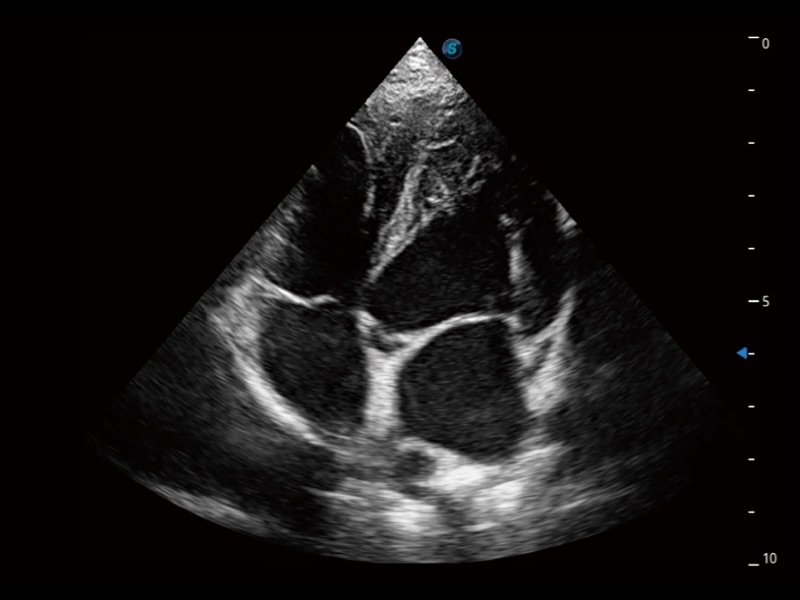

ProPet 70 进一步提升了微米成像算法,更加注重对基础原始图像的还原和保留,在有效减少斑点噪声、增强组织边界显示的同时,避免过度优化丟失真实的解剖信息。